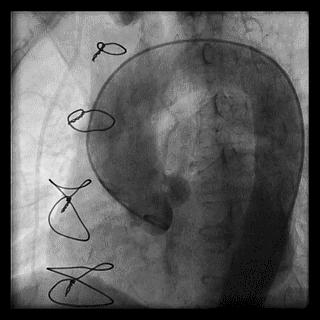

桡动脉迂曲在TRI中是一常见问题,约占3.8%~4.2%,桡动脉迂曲的部位在桡动脉近心端三分之一处,老年及女性患者的发生率要明显高于其他人群。根据桡动脉迂曲的形态可进一步将其细分“S”、“α”、“Ω”以及“Z”等多种类型,其中以“S”和“Ω”形迂曲最为常见,不同类型的桡动脉迂曲处理难度亦不相同,例如桡动脉“S”形迂曲的处理相对较为容易,其操作成功率要高于其它类型的桡动脉迂曲。

“S”

“α”

“Ω”